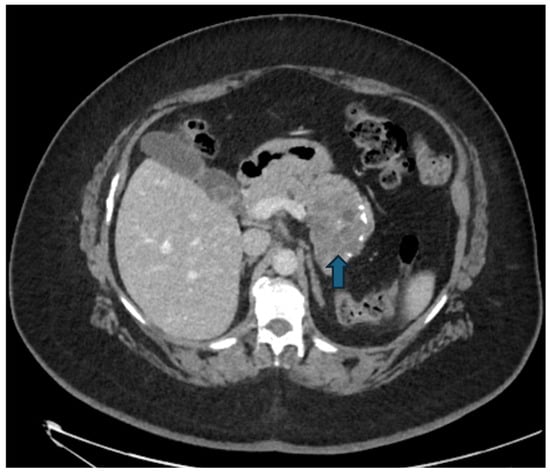

Figure 7.

(a) Axial CECT scan of a 50-year-old-woman shows a large (40 mm), multiloculated lesion located in the pancreatic tail (blue arrow); (b) MRI demonstrates a well-circumscribed, multilocular cystic lesion with thick internal septa (black arrow), showing hyperintense signal on T2-w images.

Figure 8.

CECT of a 49-year-old woman shows a cyst-like lesion with a calcified wall (arrow) in the pancreatic tail (a). In the arterial (b) and venous (c) contrastographic phases, mall enhancing mural nodules are observed.